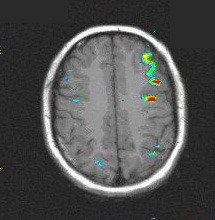

T1 weighted MRI

Transverse image at the level of the planum temporale. The left hemisphere is seen in the right side (radiological convention). The subject's task was listening to a story.The red bubble seen on the left side corresponds to areas related to complex semantic processing.